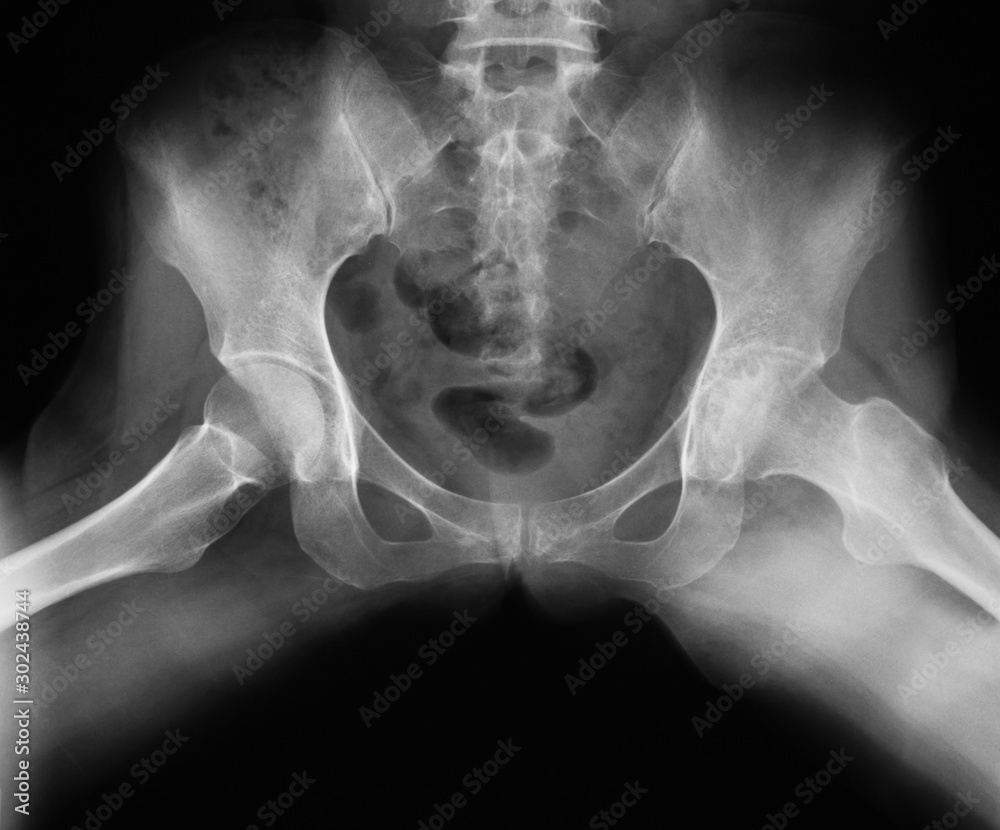

(a and b) Xrays of pelvis with both hips anteroposterior and frog leg

Xray image of both hip, frogleg Position, show hip osteoarthritis Frog Leg Lateral Hip Position Some departments will perform this routinely instead of the ap pelvis view to reduce. — the lateral hip view is a radiographic projection assessing the relationship of the femoral head to the acetabulum. The knee joint is flexed 30°. Useful in trauma patients where positioning is limited by pain. the frog leg lateral view is a special pelvis. Frog Leg Lateral Hip Position.